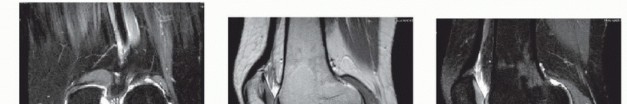

DEFINITION Osteochondral lesion of the talus (OLT) may cause significant pain and mechanical symptoms in the …